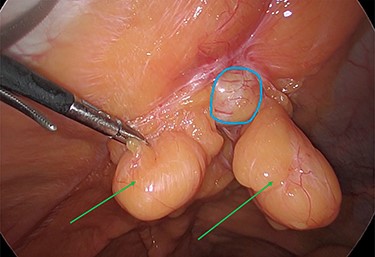

Intraoperatively, we noticed omentum incarcerated in the hernia sac (Fig. 2).

Laparoscopic view of the incarcerated omentum in the umbilical hernia (green arrow).

The viable omentum was reduced into the peritoneal cavity. Two lipomas were then observed attached to the parietal peritoneum (Figs 3 and 4). The lipomas were also reduced into the peritoneal cavity from within the hernia sac. Each one was 2 cm in diameter based on laparoscopic visualization using the 1 cm markings on a suction irrigation device.

The two peritoneal lipomas (green arrows) and the visible umbilical hernia neck (blue circle). Intracorporeal suturing of the hernia neck (green arrow) and closure of the hernial defect.